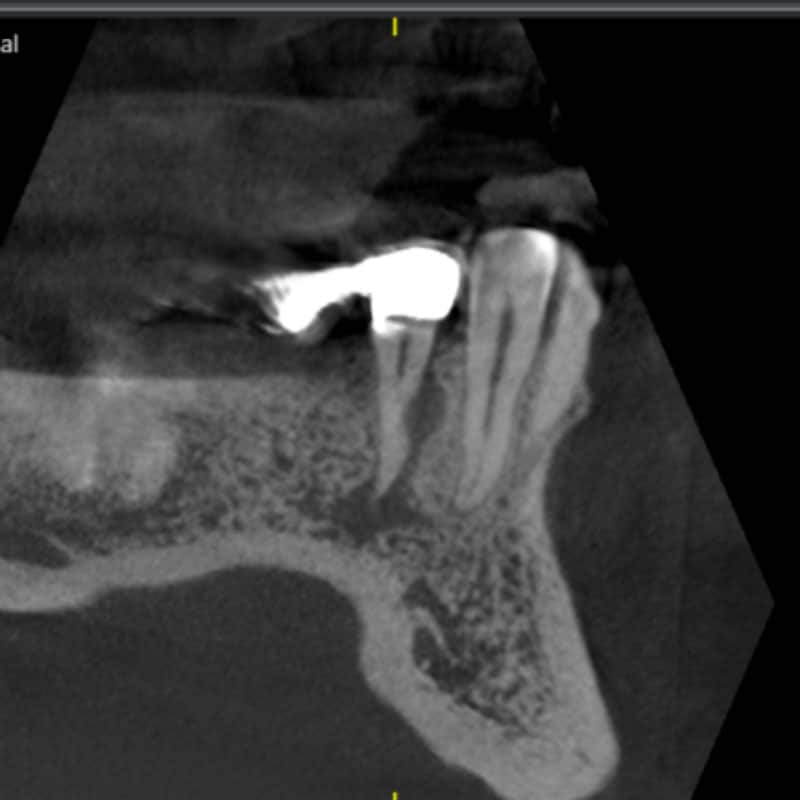

Revision einer infizierten Wurzelfüllung 27